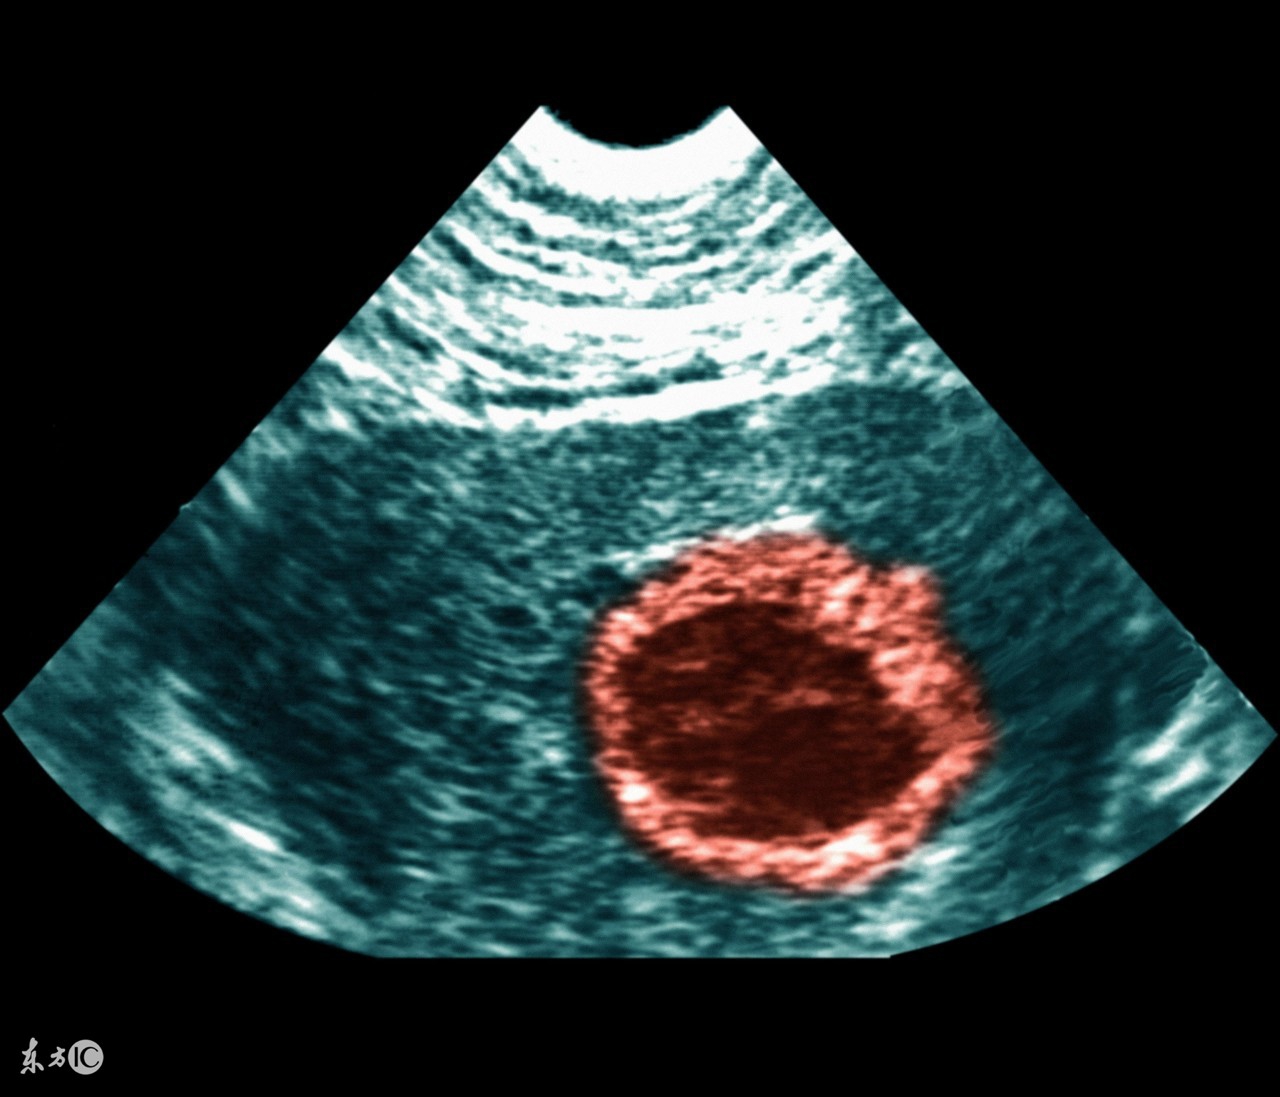

带环怀孕孩子能要吗

一般带环怀孕的话,临床上都是进行取环及终止妊娠的处理。如果带环受孕了,通常都是因为节育器位置变动了导致受精卵着床而造成的,在这种情况下,怀孕对幼儿的影响是不好的,如果执意要这个孩子,在怀孕过程内很有可能出现孕期出血或者胎儿某一部分被节育器套住的情况,为了避免日后更多的麻烦或者不必要的危险,建议做人工流产。手术结束后,仍不想要孩子,就试着换一种不同的节育器试试。